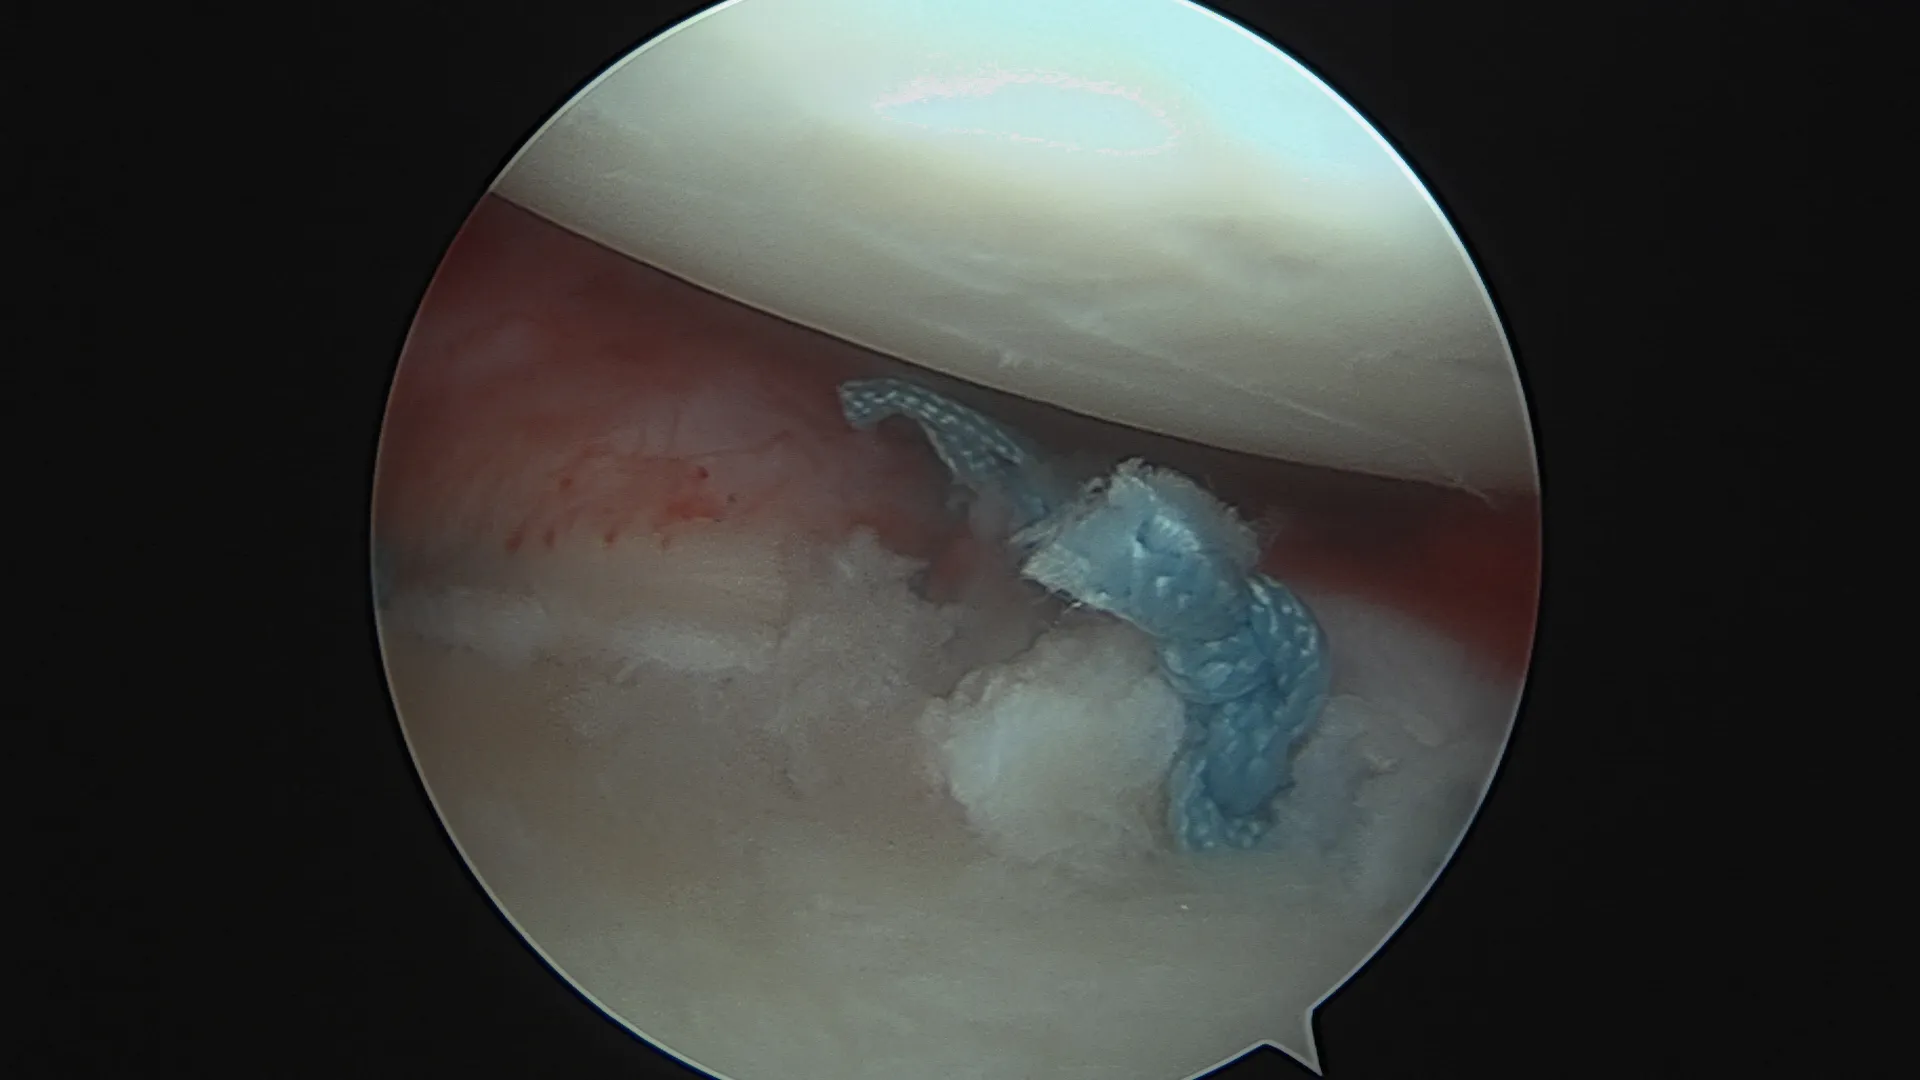

Réparation de Bankart — sous arthroscopie

Pour qui ? Instabilité antérieure sans perte osseuse glénoïdienne significative (score ISIS ≤ 3).

Comment ? L'intervention est réalisée entièrement sous arthroscopie (vidéochirurgie), par 2 à 3 incisions de quelques millimètres seulement. Le labrum arraché est réinséré sur la glène à l'aide d'ancres résorbables sur lesquelles sont fixés des fils très résistants. Les ligaments gléno-huméraux distendus sont retendus dans le même temps opératoire.

Résultat : taux de succès élevé dans les indications bien posées. Reprise sport sans contact vers 4 mois. Non indiqué en première intention pour les sports de contact ou d'armé-contré.

Le remplissage de l'encoche postérieure (Hill-Sachs remplissage)

Pour qui ? En complément du Bankart, quand l'encoche humérale postérieure est engageante.

Comment ? L'encoche est comblée en plicaturant la coiffe des rotateurs dans le défect osseux à l'aide d'ancres miniaturisées. Cette technique arthroscopique évite dans certains cas de recourir à une butée.